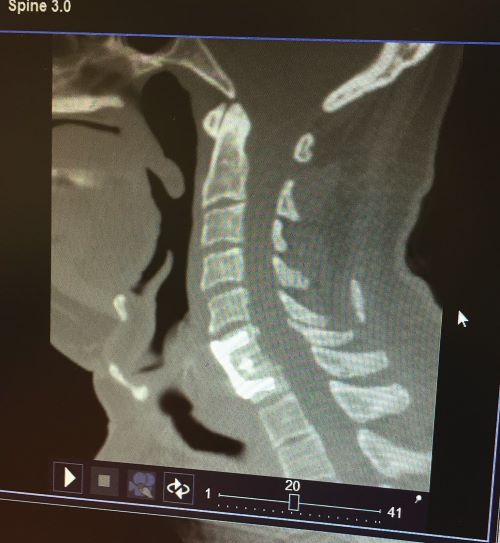

Η διαγνωστική προσέγγιση γίνεται κυρίως με την κλινική εξέταση και την διενέργεια απεικονιστικών εξετάσεων. Η απλή ακτινογραφία και η αξονική τομογραφία δίνουν πληροφορίες για τις οστικές δομές ενώ η μαγνητική τομογραφία απεικονίζει καλύτερα τα μαλακά μόρια (μεσοσπονδύλιους δίσκους, συνδέσμους, νωτιαίο μυελό και νωτιαίες ρίζες). Ο νευροφυσιολογικός έλεγχος (ηλεκτρομυογράφημα, ταχύτητες αγωγής κ.α.) διενεργείται στις περιπτώσεις στις οποίες πρέπει να αποκλειστεί περιφερική βλάβη η οποία μπορεί να συνυπάρχει.

Η νευροχειρουργική επέμβαση η οποία γίνεται συνήθως με πρόσθια προσπέλαση, με μία μικρή τομή 2-3 εκατοστών (ακολουθώντας προϋπάρχουσες δερματικές πτυχές για άριστο αισθητικό αποτέλεσμα). Διενεργείται πλήρης αφαίρεση του μεσοσπονδύλιου δίσκου, αφαίρεση οστεοφύτων, πλήρης απελευθέρωση όλων των νευρικών στοιχείων, και τοποθέτηση μεταξύ των σπονδύλων, μεσοσπονδύλιων προθεμάτων (PEEK) ή τοποθέτηση τεχνητού δίσκου.